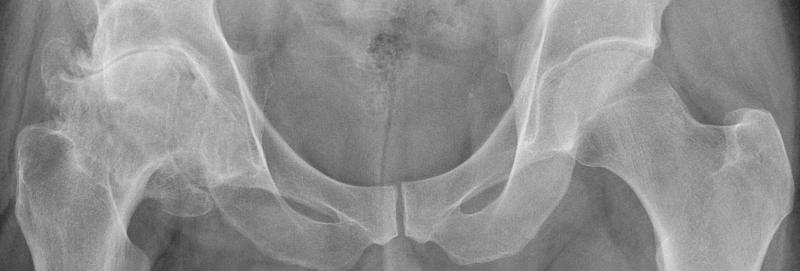

Хирургическое вмешательство, в ходе которого врач удаляет изъеденный артритом участок бедренного сустава, заменяя его искусственным имплантатом, состоящим из пластиковых и металлических комплектующих, называют эндопротезированием. Операция дает продолжительный терапевтический эффект и показана, если консервативные методы лечения не облегчают состояние больного.

Первая операция по замене тазобедренного сустава была произведена в Германии хирургом Темистоклсом Глаком в 1891 году. В качестве искусственной бедренной головки использовалась слоновья кость, закрепленная при помощи цинковых винтов, гипса и клея.